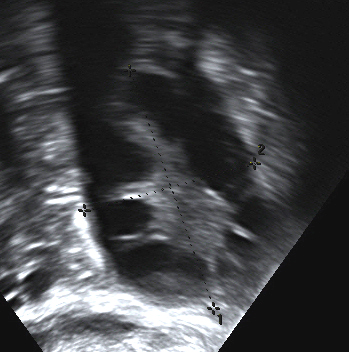

이 증후군은 초음파 검사에서 다수의(poly) 난소 낭종이 흔히 발견된다는 사실 때문에 이러한 이름이 붙었다. 이 "낭종"은 실제로 미성숙한 난소 난포이다. 난포는 원시 난포에서 발달했지만, 이 발달은 손상된 난소 기능으로 인해 초기 단계에서 멈추었다("정지"). 난포는 난소 주변을 따라 배열될 수 있으며, 초음파 검사에서 '진주 목걸이'처럼 보인다.[81]

난소 표면이 비후되고 배란이 이루어지지 않아, 정체된 난포로 인해 난소가 다낭포화된다. 초음파 영상으로 보면 난소 표면을 따라 알갱이가 빙 둘러 연결된 모습에서 "목걸이 징후"라고 불린다.

부인과 초음파 검사는 특히 작은 난소 난포를 찾는 데 사용된다. 이들은 난소 기능 장애의 결과로 여겨지며, 이는 이 질환의 전형적인 특징인 불규칙하거나 없는 월경으로 나타난다. 정상적인 월경 주기에서 지배적인 난포에서 하나의 난자가 배출된다. 즉, 난자를 방출하기 위해 터지는 낭종이다. 배란 후 난포 잔류물은 프로게스테론을 생성하는 황체로 변환되며, 약 12~14일 후에 수축하여 사라진다. PCOS에서는 소위 "난포 정지"가 발생한다. 즉, 여러 개의 난포가 5~7mm 크기로 발달하지만 더 이상 발달하지 않는다. 단일 난포도 배란 전 크기(16mm 이상)에 도달하지 못한다. PCOS 진단에 널리 사용되는 로테르담 기준[102]에 따르면, 초음파 검사에서 의심되는 난소에서 12개 이상의 작은 난포가 보여야 한다.[13] 최근 연구에 따르면, 18~35세 여성의 난소에 다낭성 난소 형태(PCOM)를 지정하려면 난소에 최소 25개의 난포가 있어야 한다고 한다.[88] 난포는 주변에 위치하여 '진주 목걸이' 모양을 나타낼 수 있다.[89] 고해상도 질식 초음파 기기를 사용할 수 없는 경우, 난포 수 대신 난소 부피가 최소 10ml 이상인 경우 다낭성 난소 형태를 가지고 있다는 허용 가능한 정의로 간주된다.[88]

부인과 초음파 검사는 작은 난소 난포를 찾는 데 사용된다.[13] 난포는 난소 기능 장애의 결과로 발생하며, 불규칙하거나 없는 월경의 원인이 된다. 로테르담 기준에 따르면, 초음파 검사에서 12개 이상의 작은 난포가 보여야 PCOS로 진단할 수 있다.[13] 최근 연구에서는 18~35세 여성의 경우 난소에 최소 25개의 난포가 있어야 다낭성 난소 형태(PCOM)로 간주할 수 있다고 한다.[88] 난포는 주변에 위치하여 '진주 목걸이' 모양을 나타낼 수 있다.[89] 고해상도 질식 초음파 기기를 사용할 수 없는 경우, 난소 부피가 최소 10ml 이상이면 다낭성 난소 형태로 간주할 수 있다.[88]